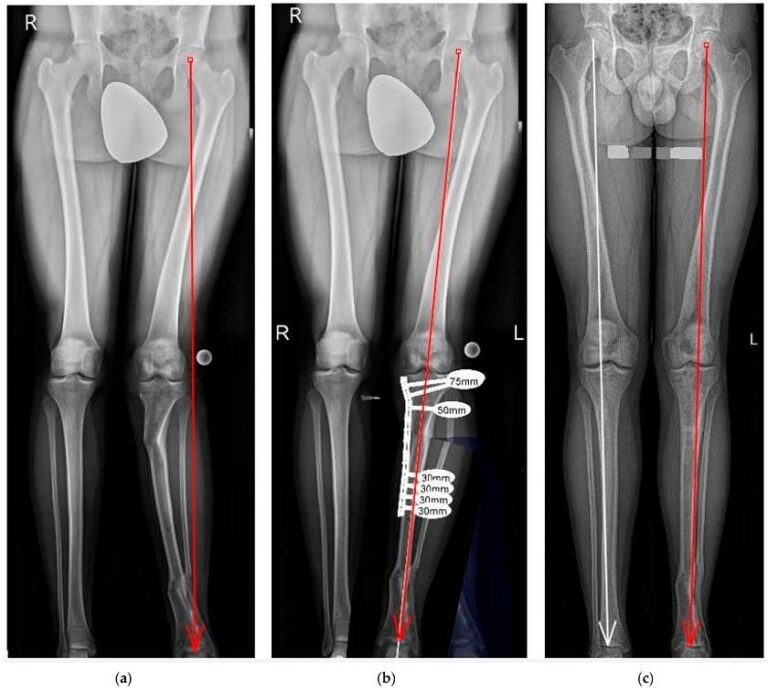

-فیکساسیون شکستگی:

ثابت کردن استخوان شکسته با پلاک، پیچ، میله یا فیکساتور خارجی